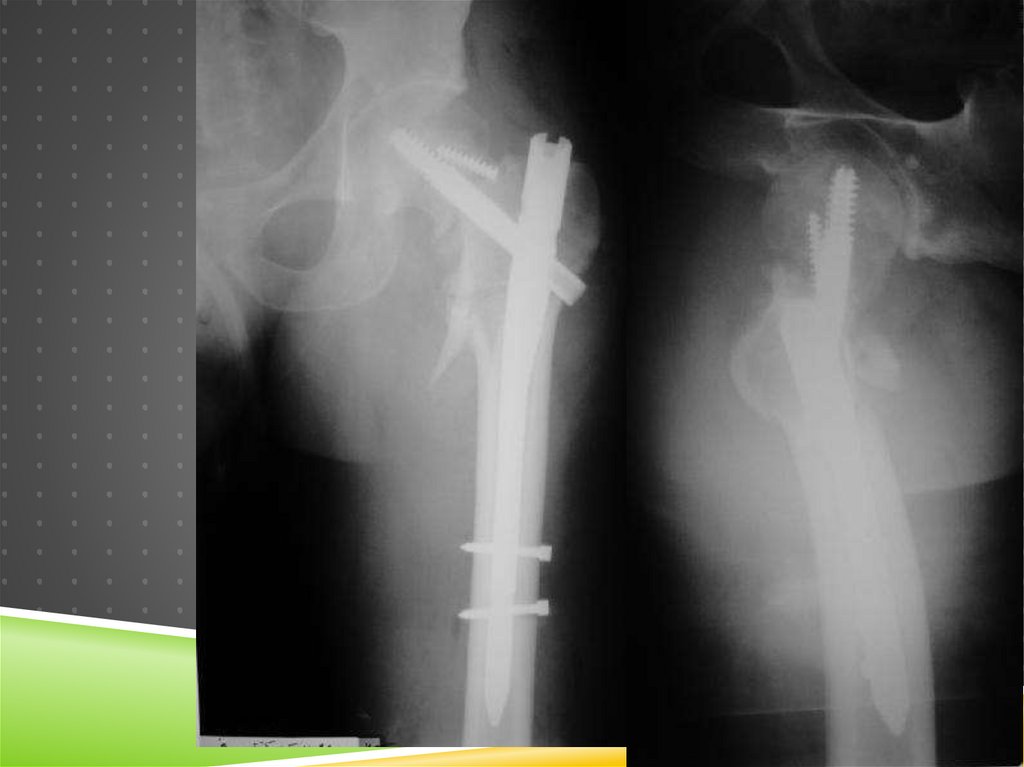

68. 6 мес.

6 МЕС.

68